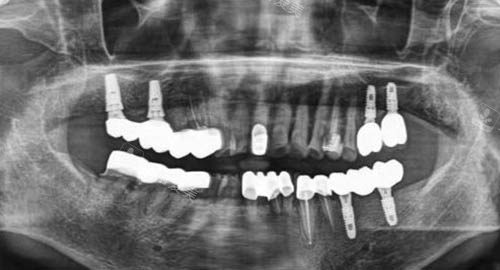

无论是牙齿矫正、种植牙还是口腔修复等项目,都能取得稳定的治疗结果。